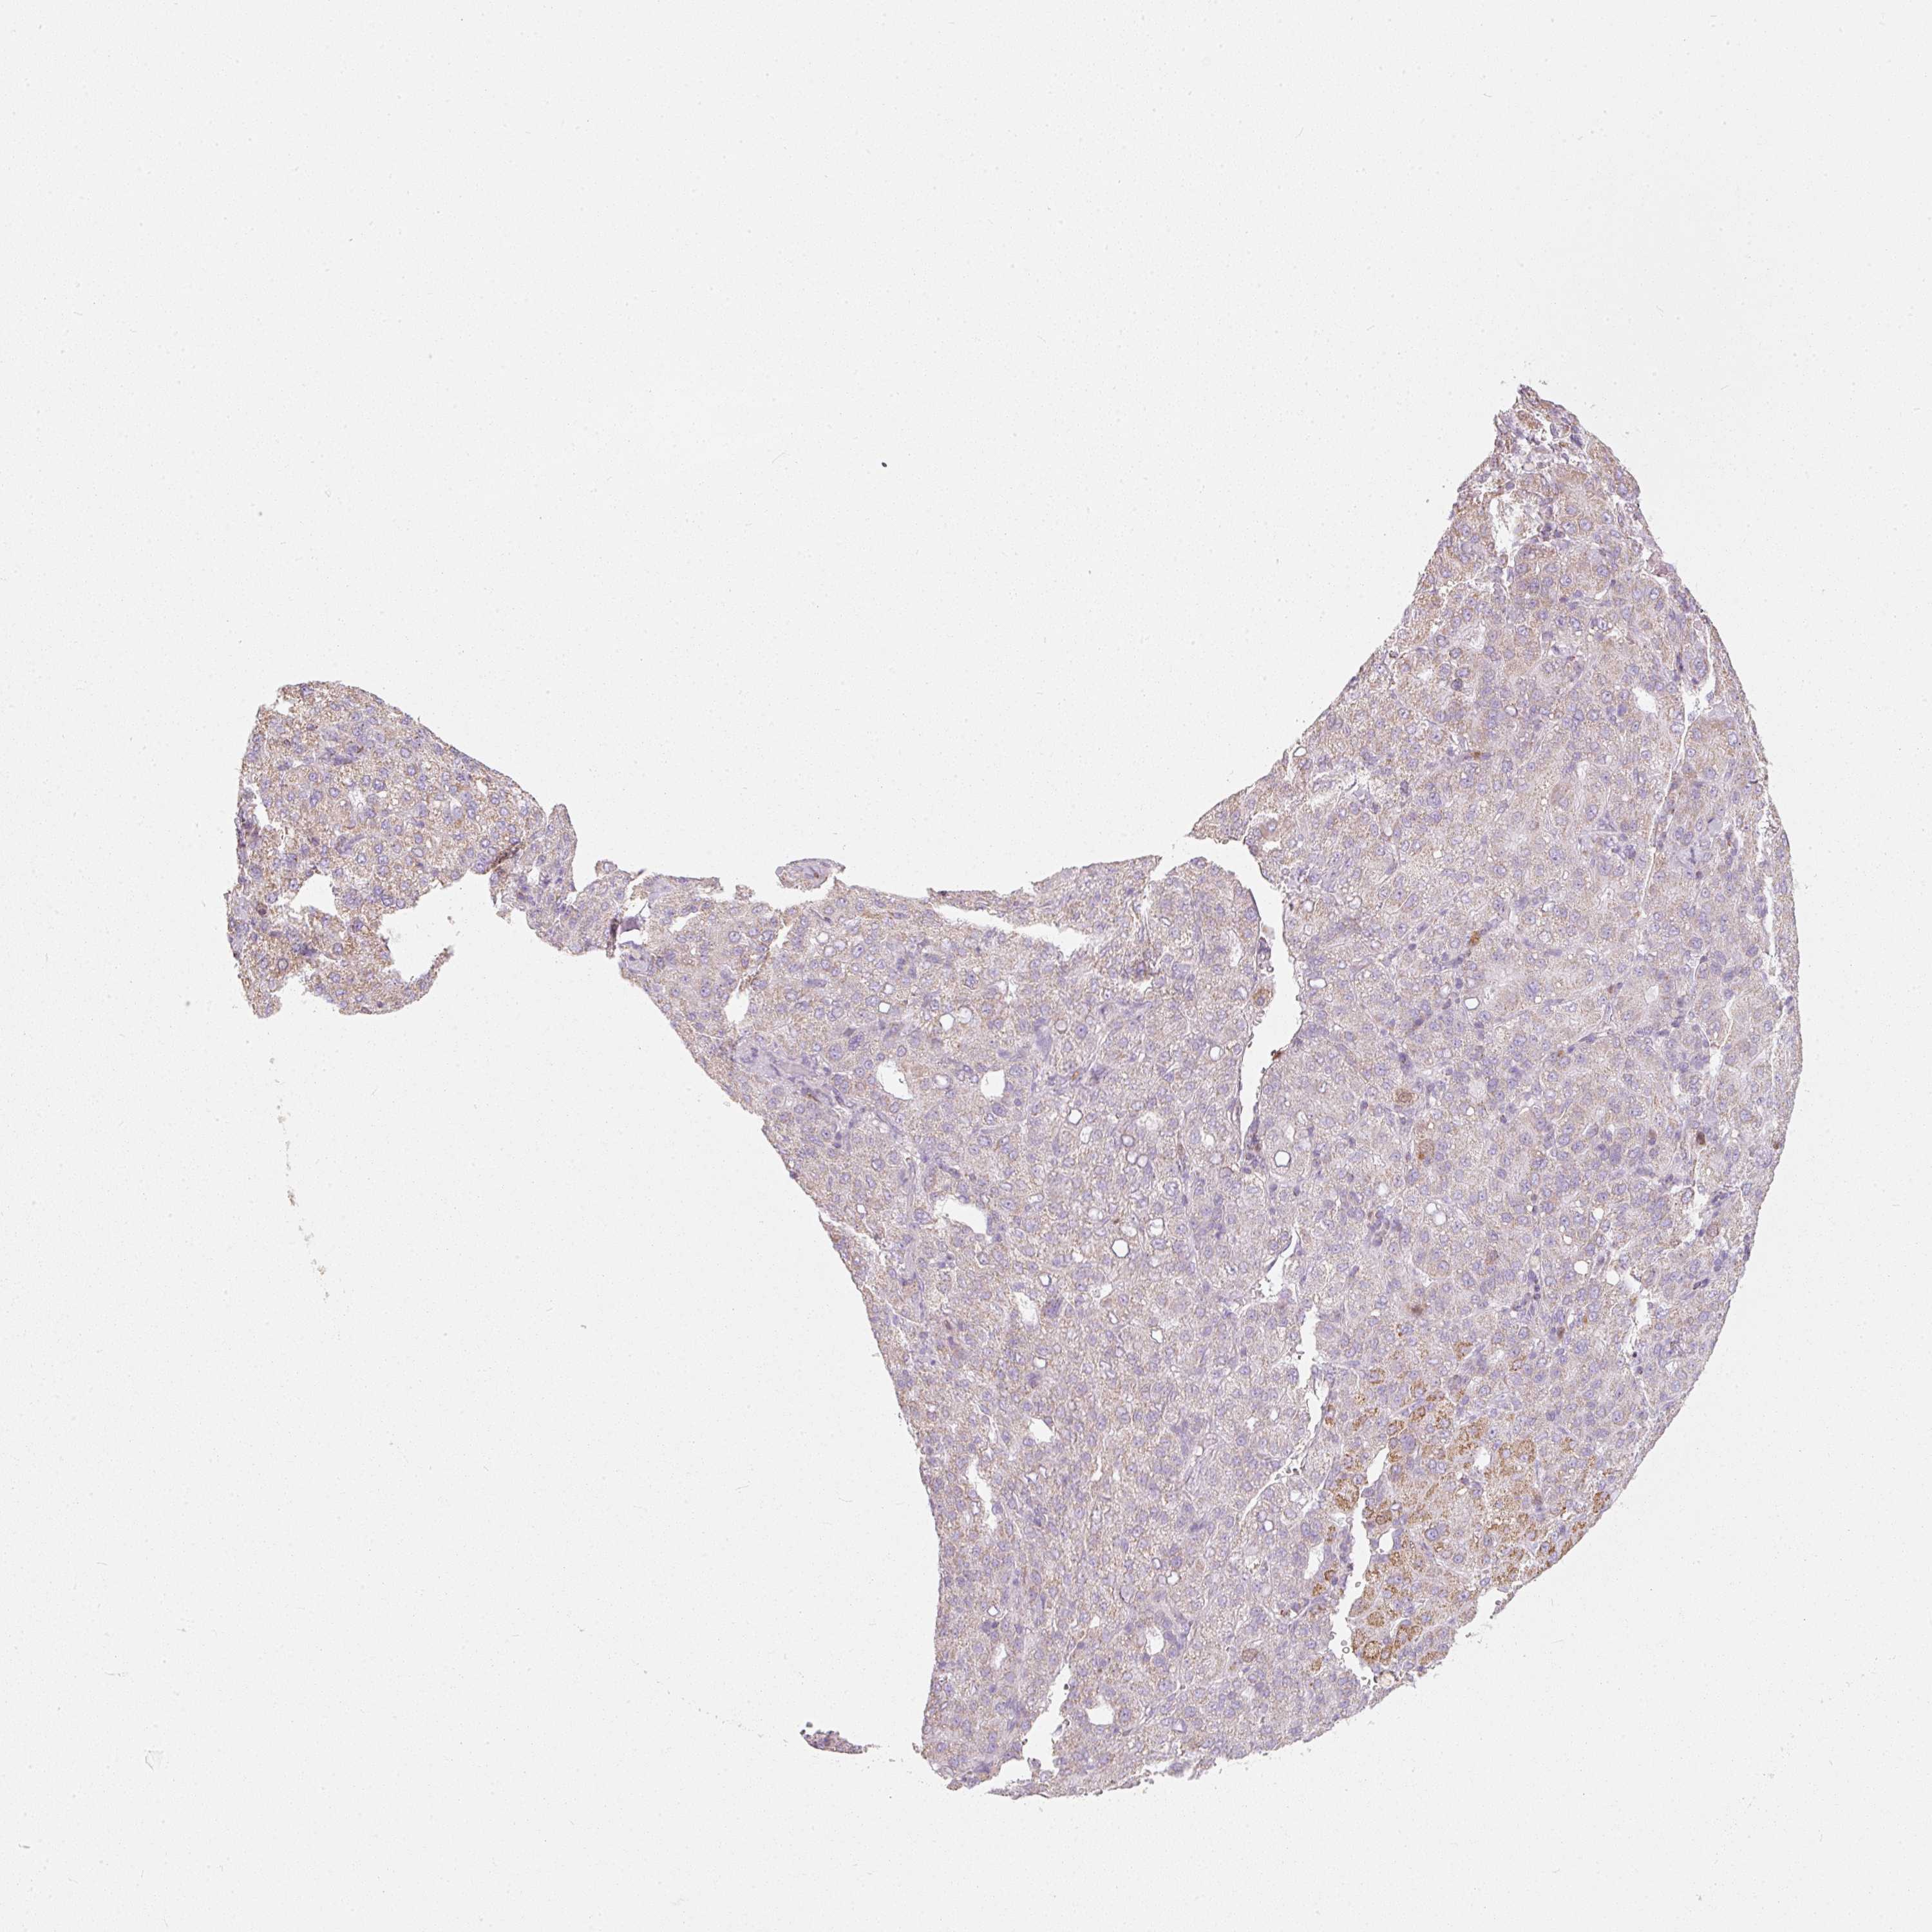

LIVER CANCER - Protein expressioni

A mouse-over function shows sample information and annotation data. Click on an image to view it in a full screen mode. Samples can be filtered based on level of antibody staining by selecting one or several of the following categories: high, medium, low and not detected. The assay and annotation is described here.

Note that samples used for immunohistochemistry by the Human Protein Atlas do not correspond to samples in the TCGA dataset.

Antibody stainingi

Antibody staining in the annotated cell types in the current human tissue is reported as not detected, low, medium, or high, based on conventional immunohistochemistry profiling in selected tissues. This score is based on the combination of the staining intensity and fraction of stained cells.

Each image is clickable and will lead to virtual microscopy that enables deeper exploration of all samples and also displays staining intensity scores, fraction scores and subcellular localization as well as patient and tissue information for each sample.

Antibody HPA054422

Antibody HPA060360

Staining

High

Medium

Low

Not detected

Intensity

Strong

Moderate

Weak

Negative

Quantity

>75%

75%-25%

<25%

None

Location

Nuclear

Cytoplasmic/membranous

Cytoplasmic/membranous,nuclear

Carcinoma, Hepatocellular, NOS

Cholangiocarcinoma